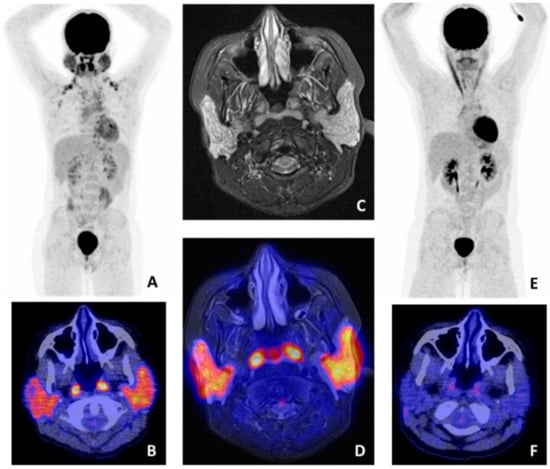

- Cohen, C.; Mekinian, A.; Uzunhan, Y.; Fauchais, A.L.; Dhote, R.; Pop, G.; Eder, V.; Nunes, H.; Brillet, P.Y.; Valeyre, D.; et al. 18F-fluorodeoxyglucose positron emission tomography/computer tomography as an objective tool for assessing disease activity in Sjögren’s syndrome. Autoimmun. Rev. 2013, 12, 1109–1114. [Google Scholar] [CrossRef]

- Keraen, J.; Blanc, E.; Besson, F.L.; Leguern, V.; Meyer, C.; Henry, J.; Belkhir, R.; Nocturne, G.; Mariette, X.; Seror, R. Usefulness of 18F-Labeled Fluorodeoxyglucose–Positron Emission Tomography for the Diagnosis of Lymphoma in Primary Sjögren’s Syndrome. Arthritis Rheumatol. 2019, 71, 1147–1157. [Google Scholar] [CrossRef]